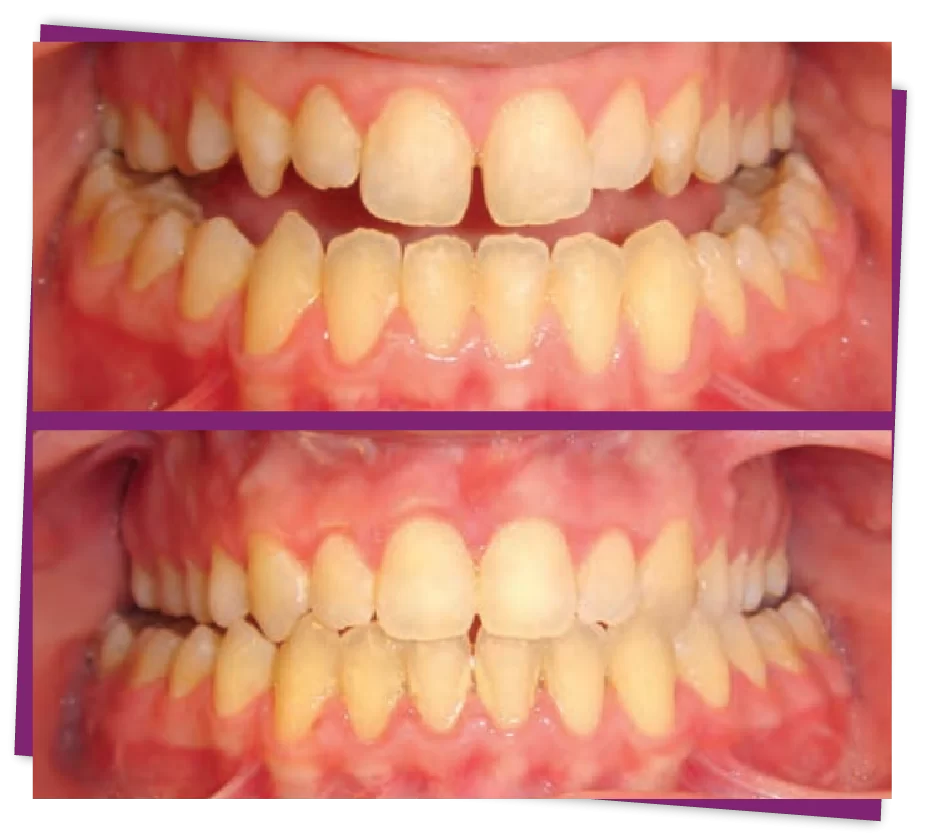

Móm là một dạng sai lệch khớp cắn do khớp cắn bị ngược, vòm hàm dưới phủ ngoài vòm hàm trên. Hay khi khép miệng lại, hàm trên thường sẽ nằm ngoài hàm dưới còn khi bị móm thì hàm dưới sẽ nằm ngoài hàm trên.

Khi chúng ta bị móm sẽ thấy tương quan hàm trên ở bên trong hàm dưới, trong khi răng hàm dưới phải ở trong so với hàm trên thì mới đạt chuẩn.

Móm xương hàm là tình trạng sai lệch khớp cắn, do hàm dưới phát triển quá mức, ở trạng thái bình thường, hàm dưới sẽ nhô ra ngoài so với hàm trên, khiến gương mặt mất cân đối.